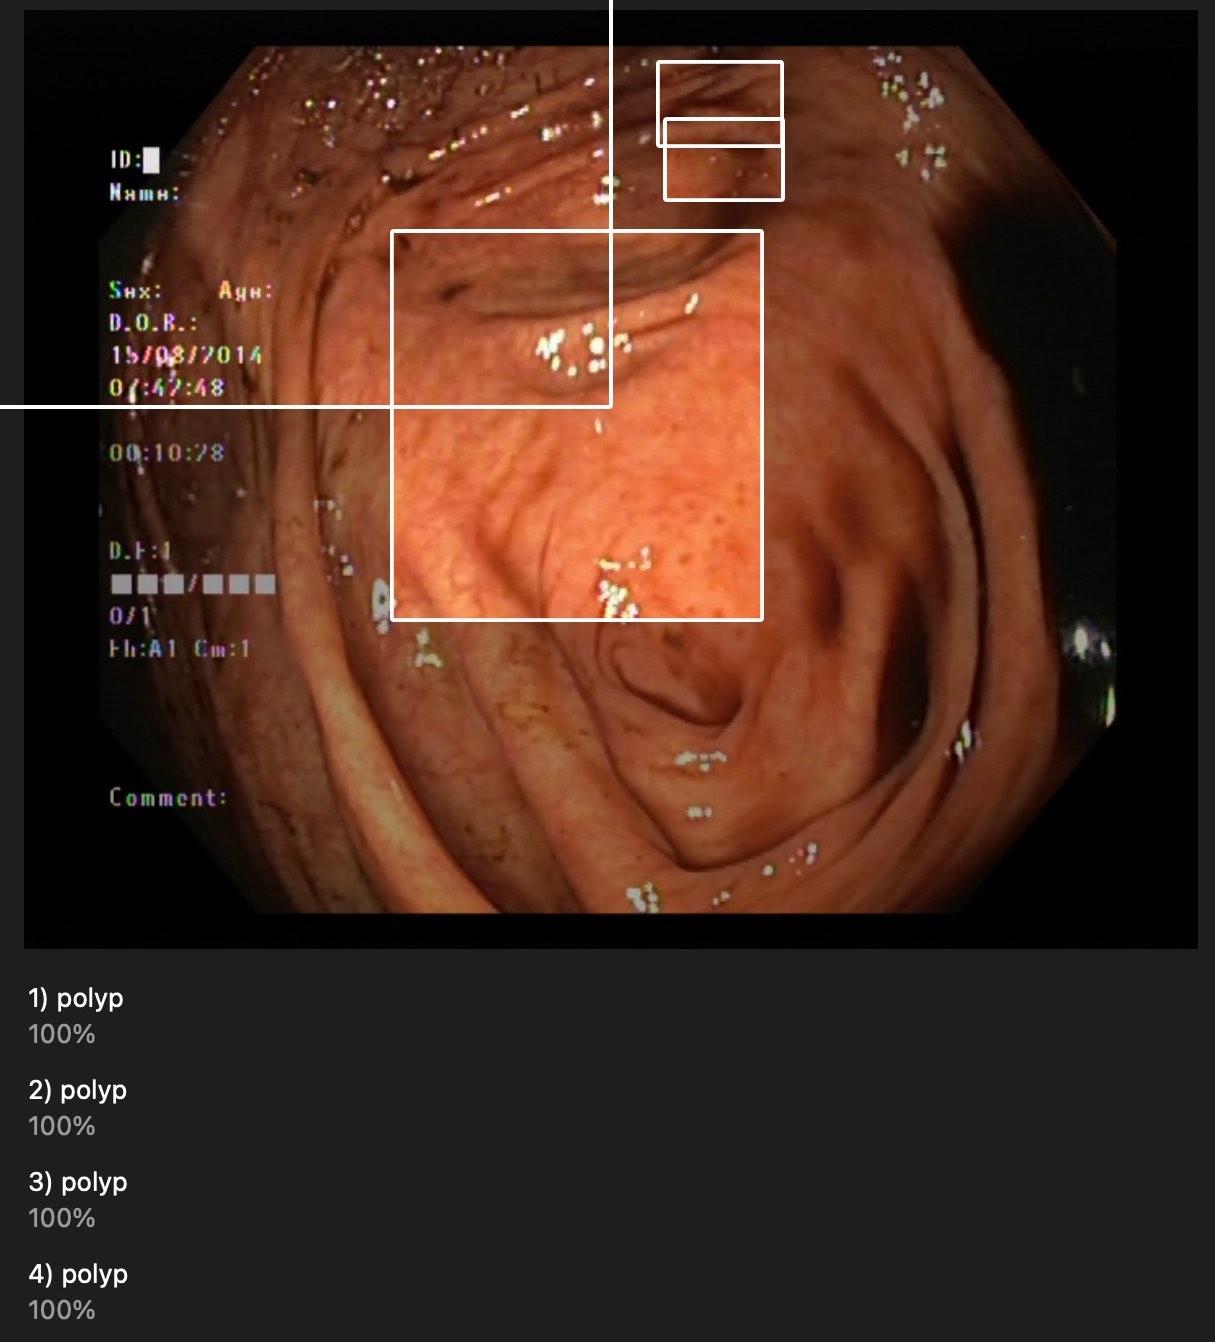

They are near polyps but most of them are not surrounding correctly.